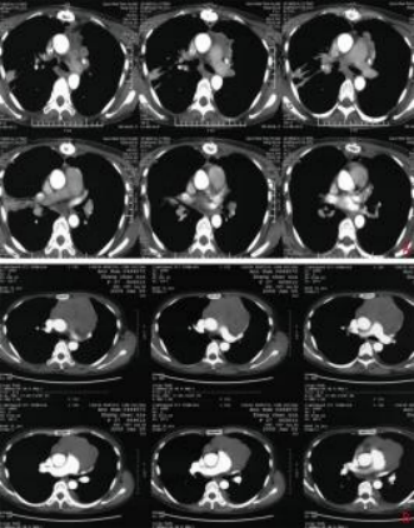

Case Report: A 43-year-old female patient with no significant past medical history, denies smoking or chronic lung disease. The patient presented to Wuwei Cancer Hospital in February 2009 with complaints of palpitations and shortness of breath for 4 months, 10 years following postoperative radiotherapy for thymic carcinoma. Chest CT revealed a mass in the anterior superior mediastinum, suggesting a thymic tumor with invasion of the pericardium and left lung (Figure 1A). On February 16, 2009, the patient underwent "extensive resection of thymic tumor + partial resection of the left upper lobe of the lung, phrenic nerve, and pericardium." Postoperative pathology showed: (anterior superior mediastinum) thymic non-keratinizing squamous cell carcinoma. The tumor invaded the pericardium and lung, with no involvement of major blood vessels or lymph nodes. Pathological diagnosis: Masaoka stage IIIa, type C: thymic carcinoma. Postoperative chest CT indicated: postoperative thymic carcinoma, triangular effusion under the left sternum and effusion in the anterior pericardial space, extensive thickening and adhesion of the left pleura with a small amount of pleural effusion, local bone defect after sternal surgery, and soft tissue swelling (Figure 1B). Postoperative diagnosis: pT3N0M0 stage IIIa, based on the 8th edition of the American Joint Committee on Cancer (AJCC) staging. The patient received postoperative intensity-modulated radiotherapy (IMRT) 35 days after surgery, with a dose of 50 Gy delivered in 25 fractions, targeting the original tumor bed and the upper mediastinum. Thereafter, the patient received no further treatment and underwent regular chest CT follow-ups. In December 2019, the patient again experienced palpitations and shortness of breath. Chest CT revealed multiple nodules in the left pleura, diaphragmatic crura, and peritoneum, with the largest lesion (6.3 cm × 5.2 cm) located near the pericardium in the left pleura, as well as multiple small lymph nodes in the left neck root, mediastinum, and retroperitoneum, suggesting recurrence and metastasis of thymic carcinoma. The clinical diagnosis was rcT2N2M1a stage IVa. After multidisciplinary team (MDT) consultation, considering the patient’s long disease-free survival after the previous surgery and radiotherapy, and the tumor’s indolent biological behavior, palliative carbon ion radiotherapy was administered to the largest tumor near the left pericardium, which was compressing and invading the heart, to alleviate the patient’s symptoms of palpitations and shortness of breath. Carbon ion therapy was chosen due to its unique biological and physical advantages. The biological characteristics of carbon ions include higher linear energy transfer (LET) and greater relative biological effectiveness (RBE), as well as a low oxygen enhancement ratio (OER) that is unaffected by tumor hypoxia, thereby improving local tumor control. [1]The physical characteristics of carbon ions, such as the Bragg peak and minimal lateral scattering, allow for more precise radiation dose distribution1. Thus, while delivering a high dose to the tumor, the radiation dose to the heart and lungs can be minimized, protecting critical organs. Treatment plan: The patient was placed in the prone position with hands crossed above the head, left hand on top, and a pillow under the forehead. Dual immobilization was achieved using a large vacuum cushion and thermoplastic film. CT scans were performed with a slice thickness of 3 mm, including plain, contrast-enhanced, and 4D sequences. The CT images were transferred to the "rtStation" planning system for target delineation. Target delineation: The gross tumor volume (GTV) included the largest tumor visible on imaging near the left pericardium; the clinical target volume (CTV) was defined as GTV with a 5 mm margin; the planning target volume (PTV) was defined as CTV with a 5 mm margin. Adjustments were made to protect critical organs, with a 1 cm safety margin left near the left ventricle. Treatment planning: Carbon ion treatment planning was performed using the Ci-plan software. The treatment plan required that 90% of the PTV receive the prescribed dose. One left lateral field and one vertical field were used, with a total dose of 60 GyE delivered to the lesion (Figure 2). The single dose was 4 GyE, administered once daily, 5 times per week (Monday to Friday), for a total of 12 fractions over 3 weeks. The dose of carbon ions was expressed in photon equivalent dose (GyE), where GyE is defined as the physical dose multiplied by the RBE of carbon ions, with the with a relative biological effectiveness (RBE) of carbon ions typically set at 3.0[2]. During and after treatment, the patient received no other therapies. After treatment, the patient’s symptoms of palpitations and shortness of breath were relieved. During treatment, only mild skin pigmentation was observed at the treatment site, classified as grade 1 skin reaction according to the Radiation Therapy Oncology Group (RTOG) acute radiation injury grading criteria, and grade 1 radiation dermatitis according to the Common Terminology Criteria for Adverse Events (CTCAE) version 5.0. The skin reaction resolved completely 2 months after radiotherapy. Chest CT performed on the day of treatment completion showed not only shrinkage of the largest lesion at the irradiated site (left pericardium), but also varying degrees of shrinkage in metastatic lesions at other sites that received low-dose or no irradiation (left chest wall and left diaphragmatic crus), with continued shrinkage observed during follow-up up to 1 year (Figures 3A–3D). The maximum diameters of the left pericardial lesion before treatment and at 1 year post-treatment were 6.3 cm, 4.6 cm, and 3.9 cm, respectively; the maximum diameters of the left chest wall lesion were 2.8 cm, 1.9 cm, and 0.8 cm, respectively; and the maximum diameters of the left diaphragmatic crus lesion were 4.1 cm, 3.9 cm, and 3.4 cm, respectively. According to the RECIST 1.1 criteria for solid tumor response evaluation, the treatment outcome was assessed as partial response (PR). Due to the unique physical advantages of carbon ions, the radiation dose to critical organs such as the heart and lungs was reduced, better protecting normal tissues. The patient experienced no acute radiation injuries of grade ≥2 during the entire treatment period, demonstrating the safety and efficacy of the treatment approach.

A: Preoperative chest contrast-enhanced CT (January 9, 2009); B: Postoperative chest contrast-enhanced CT (February 21, 2009)

Figure 1 Preoperative and postoperative imaging